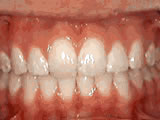

Crowding of the teeth

Patient started treatment at age 11 and wore braces for 26 months. He loves his new smile.